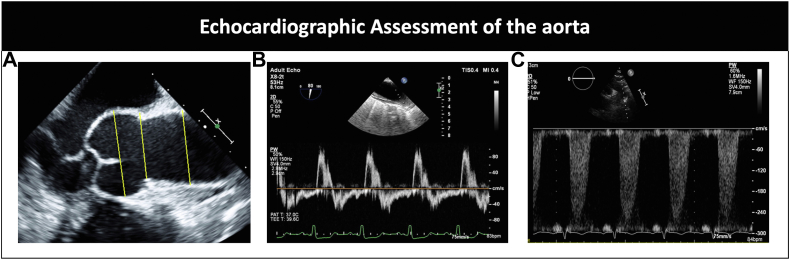

Figure 5.

(A) Parasternal imaging with measurement of the aortic root at the sinus, sinotubular junction, and ascending aorta using leading-edge-to-leading-edge measurement (yellow lines). (B) Pulse wave Doppler of the ascending aorta showing diastolic flow reversal in a patient with aortic regurgitation. (C) Doppler showing flow acceleration in the descending aorta in a patient with concomitant coarctation of the aorta.

Peak systolic gradient, long time to half peak diastolic velocity, and descending aorta measurement for identification of coexisting coarctation of the aorta (Figure 5).